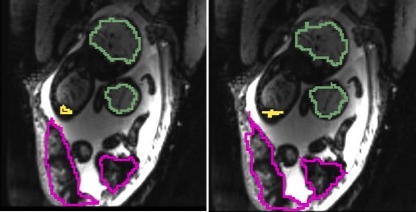

Fig. 2 illustrates results for two example cases from the study. We observe that the reference frame was warped accurately by the algorithm to represent a frame in the series that is substantially different in the regions of the placenta and the fetal liver. The delineations achieved by transferring manual segmentations from the reference frame to the coordinate system of the current frame ( in the figure) are in good alignment with the manual segmentations for the current frame. Fig. 3 reports volume overlap statistics for the placentae, fetal brains, and fetal livers, for each case in the study. We observe that temporal alignment improves volume overlap in important ROIs and offers consistent improvement for all cases over pairwise registration to the reference frame. We also note that temporal alignment offers particularly substantial gains in cases with a lot of motion, i.e., low original volume overlap.